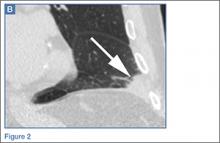

Radiographs and a noncontrast computed tomography (CT) scan of the chest were obtained. A representative posterior-anterior radiograph (Figure 1a) and a coronal noncontrast CT image (Figure 2a) are shown above.

The frontal chest radiograph demonstrated abnormal peripheral opacity at the left lung base (white arrow, Figure 1b), and the noncontrast chest CT demonstrated a peripheral, wedge/pyramid-shaped subpleural ground-glass opacity (white arrow, Figure 2b). Based on the persistent peripheral opacity despite treatment, and the patient’s clinical symptoms of acute sharp chest pain/hemoptysis, a pulmonary infarct was considered as part of the differential diagnosis, and a contrast-enhanced pulmonary embolism (PE) protocol CT was obtained for further evaluation. A coronal image from the contrast-enhanced CT demonstrated the wedge-shaped peripheral opacity (white arrow, Figure 3) as well as filling defects in the bilateral pulmonary arteries (red arrows, Figure 3), indicating the presence of PE.